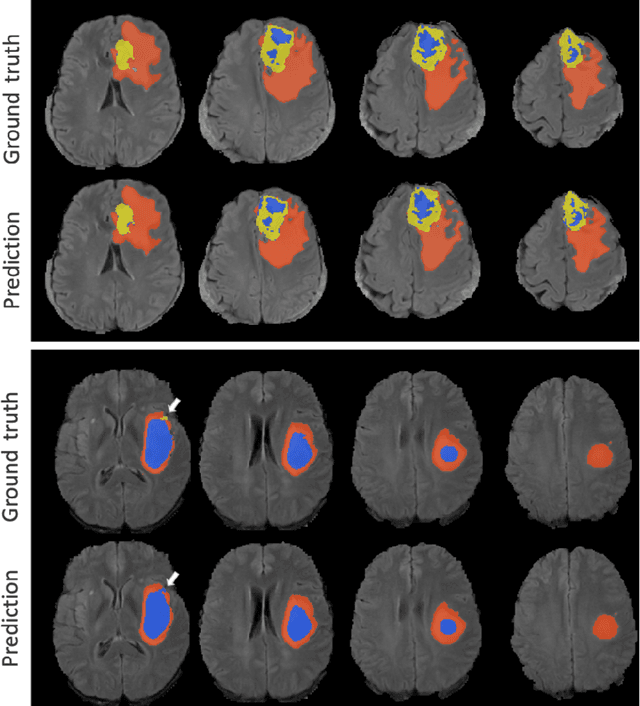

Abstract:Gliomas appear with wide variation in their characteristics both in terms of their appearance and location on brain MR images, which makes robust tumour segmentation highly challenging, and leads to high inter-rater variability even in manual segmentations. In this work, we propose a triplanar ensemble network, with an independent tumour core prediction module, for accurate segmentation of these tumours and their sub-regions. On evaluating our method on the MICCAI Brain Tumor Segmentation (BraTS) challenge validation dataset, for tumour sub-regions, we achieved a Dice similarity coefficient of 0.77 for both enhancing tumour (ET) and tumour core (TC). In the case of the whole tumour (WT) region, we achieved a Dice value of 0.89, which is on par with the top-ranking methods from BraTS'17-19. Our method achieved an evaluation score that was the equal 5th highest value (with our method ranking in 10th place) in the BraTS'20 challenge, with mean Dice values of 0.81, 0.89 and 0.84 on ET, WT and TC regions respectively on the BraTS'20 unseen test dataset.